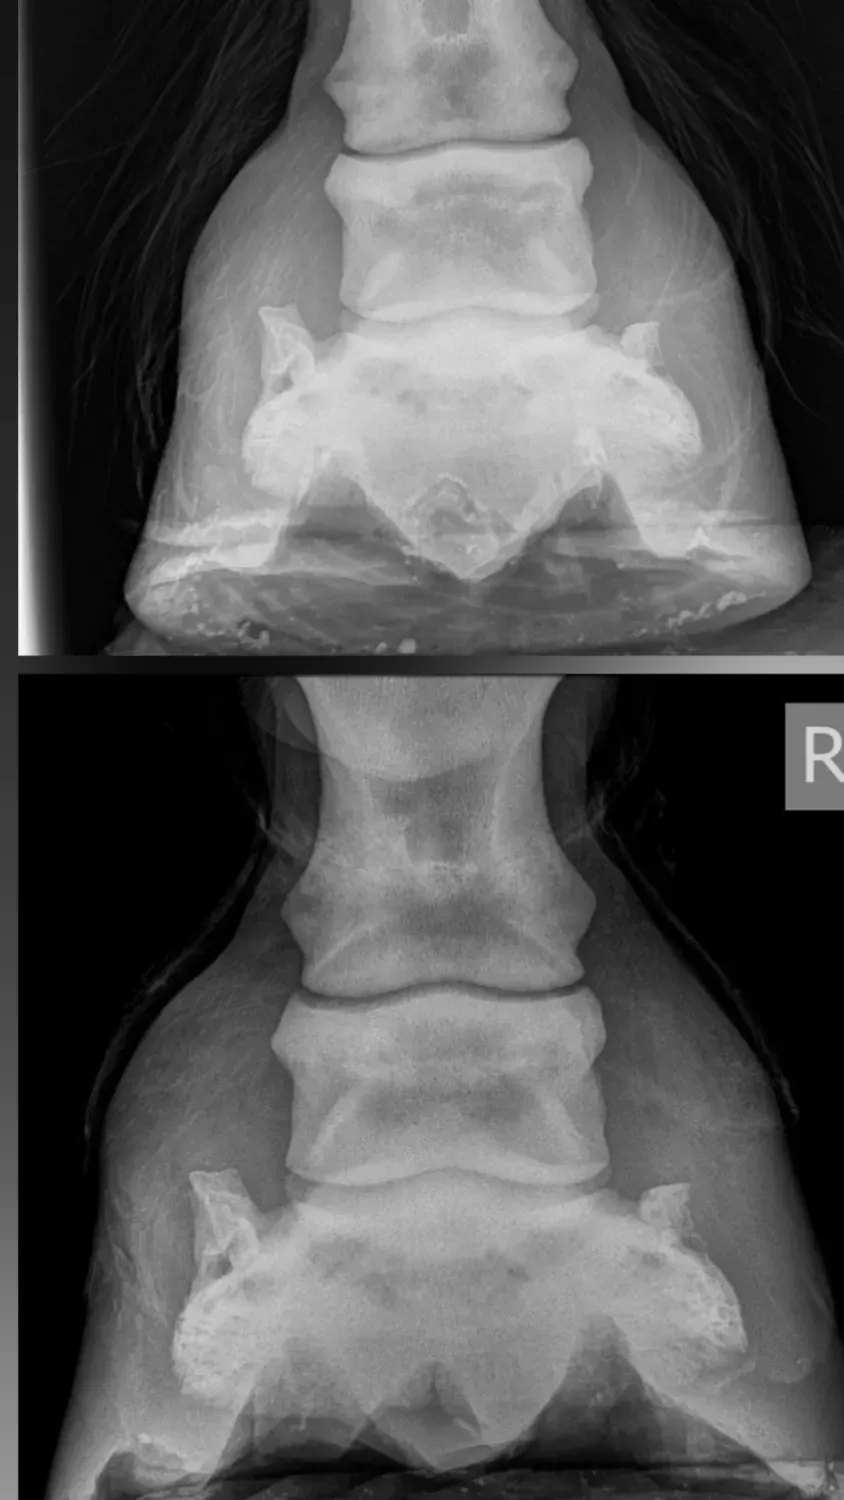

Natural alignment is important for both horse and rider. You can see from this horse’s radiograph the altered alignment of the bones on the top photo. This sadly produces excess wear and tear on the structures within the foot.

The hoof supports the horse's entire body it’s their base of support. You will be familiar with the results of foot issues on the horse’s body. Approximately 70% of equine lameness issues are believed to derive from the foot. The affects of incorrect foot balance can happen in a relatively short space in time in some horses, whereas in others the damage slowly and quietly escalates. Causing compensatory patterns and musculoskeletal damage through the body. Correct foot balance is of paramount importance for health, the longevity, and comfort of the horse. We also need to consider our own feet in terms of health and longevity.